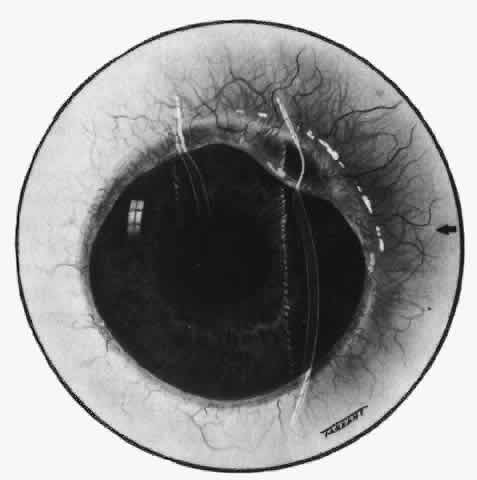

SURGICALLY INDUCED NECROTIZING SCLERITIS (SINS) Scleritis can occur after any type of ocular surgery in susceptible individuals, particularly those with intermittent systemic connective tissue disease.23–25,31–33 The scleritis is almost always of the necrotizing variety and is often extremely resistant to treatment. It can follow cataract, trabeculectomy, retinal detachment, strabismus, or any type of ocular surgery. The longest interval between the surgery and the scleritis developing at the site of the original surgery has been 24 years. Although the scleritis usually occurs adjacent to the site of surgery, it can, particularly in detachment and strabismus patients, occur at the site of the original surgery. Because this response to a surgical stimulus occurs at a site remote from the surgery, it suggests that the resident tissue macrophage has become the antigen-presenting cell that stimulates the inflammatory response. COURSE AND PROGNOSIS The corneal changes that occur in scleritis presumably have the same etiology as the scleral condition and, fortunately, respond to the same treatment. If an acute stromal keratitis is treated vigorously and early permanent changes can be avoided, the disruption of the corneal lamellae in sclerosing keratitis may partly resolve and become less obvious, but some permanent scarring remains. Corneal defects in keratolysis sometimes fill in with steroid therapy but more often leave a thin cornea that is permanently scarred and requires corneal grafting (see Figs. 65 and 66). Although the majority of patients with necrotizing scleral disease have some other systemic disorder, it is not always clear why the eye becomes involved, nor is it clear whether the scleral inflammation is due to the presence of a particular organism or to immune reactions induced by these organisms. For example, in scleritis associated with herpes zoster, no virus has been demonstrated in the sclera at the time of the primary infection. Nevertheless, these patients have developed a typical scleritis indistinguishable both clinically and cytologically from any other form of noninfectious scleritis. Scleritis can also be induced by accidental or surgical trauma in susceptible individuals. All forms of scleritis, if left untreated, will leave some scleral defect--increased transparency from changes in collagen and ground substance, actual thinning, or even ectasia. In necrotizing scleritis, the condition is progressive and exceptionally painful and leads to destruction of the eye through the complications it produces. Decreased visual acuity is not confined to severe posterior or necrotizing disease, as might be expected, but is common in the diffuse and nodular varieties of scleritis. The reasons for this decrease in acuity are cataract, macular changes (often following uveitis), optic disc changes, and, in posterior disease, retinal changes. However, early and persistent treatment is very effective in preserving the eye and vision, but careful monitoring of patients is essential to ensure that the minimum drug therapy is used to control the disorder. |